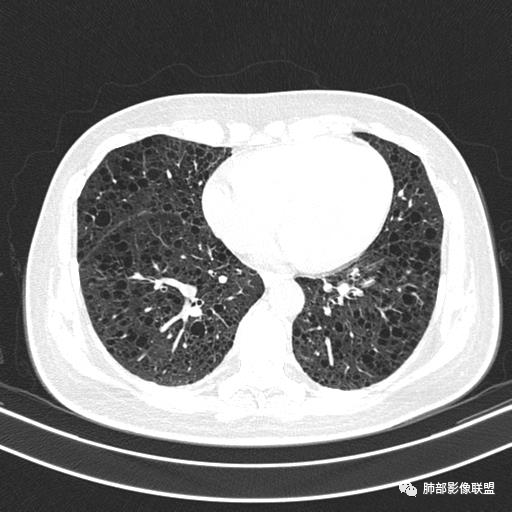

中年女性,不吸烟

双肺弥漫囊腔,累及肋膈角,囊腔形态相对规则单一。

CT平扫示双肺弥漫分布大小不等囊状薄壁透光区,无内、中、外带分布差异,间质稍示增厚。拟LAM

中年女性育龄期妇女,咳嗽气喘,无吸烟史,有苯吸入史。影像:双肺弥漫均匀小囊腔,无明显分布优势,囊腔形态欠规则,壁薄,部分囊腔边缘血管征,伴双肺弥漫磨玻璃影,无结节,考虑lam,鉴别苯中毒肺损伤,囊腔多有分布优势,小叶中心分布为主,形态规整等

女,46,活动性气喘1年。苯吸入史半年。胸部CT:两肺弥漫囊腔,上至肺尖,下至肋膈角,形态类似小囊腔。考虑:LAM,鉴别LIP,BHD,PLCH等。

双肺弥漫大小不一薄壁含气囊腔,囊间肺组织正常,正常肺背景,肺尖肺底受累;青年女性,气喘,支持LAM

CT表现:双肺弥漫大小不等的薄壁囊腔,囊壁<2mm,外形规则,血管影多位于囊腔周围,囊腔之间肺组织正常,随着疾病进展到晚期,囊腔变大、增多,不可胜数,囊腔可融合成较大的囊,与肺气肿相似,形成间质性肺纤维化。部分病例可出现结节影。